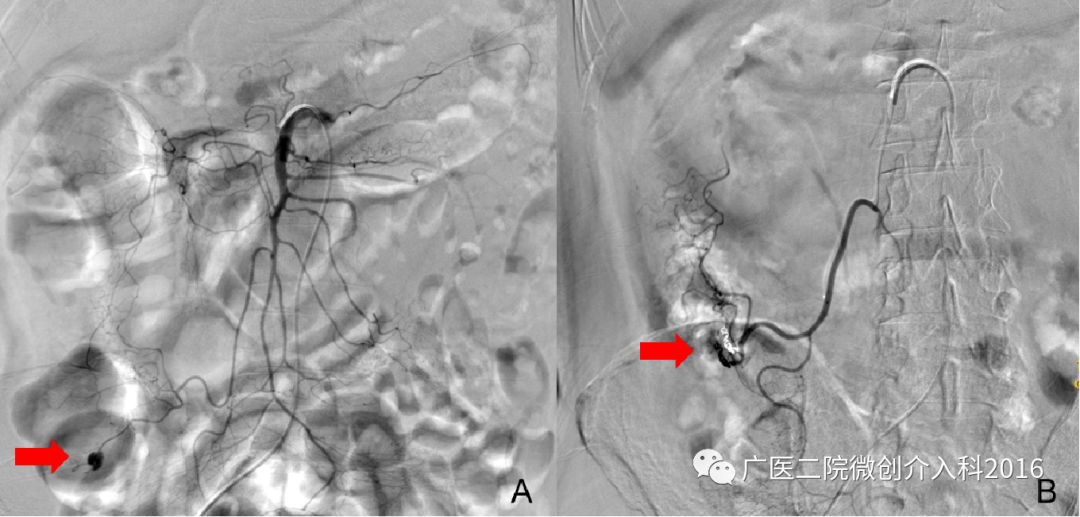

患者拉鲜血便1天余,出血量大约1000ml。肠镜提示直肠出血并行止血夹钳夹止血术,但患者仍出血不止。图A行肠系膜下动脉造影显示直肠区域造影剂浓聚、外渗,明确诊断为直肠出血,出血血管为直肠上动脉。经微导管注入弹簧圈和明胶海绵颗粒栓塞出血动脉,图B再次造影示原出血征象消失,患者出血停止。

患者为直肠癌并肿瘤出血,经内科药物治疗止血不佳,患者病情危重不能行外科手术。图A行肠系膜下动脉造影显示直肠区域肿瘤染色明显,明确诊断为直肠癌并出血,责任血管为直肠上动脉。该患者消化道出血为直肠肿瘤所致,故予以肿瘤血管栓塞达到止血目的。经微导管注入微球和弹簧圈栓塞肿瘤血管,图B再次造影示肿瘤染色较前明显减少,图C再次造影原肿瘤染色消失。经后续治疗和观察3天,患者出血停止。